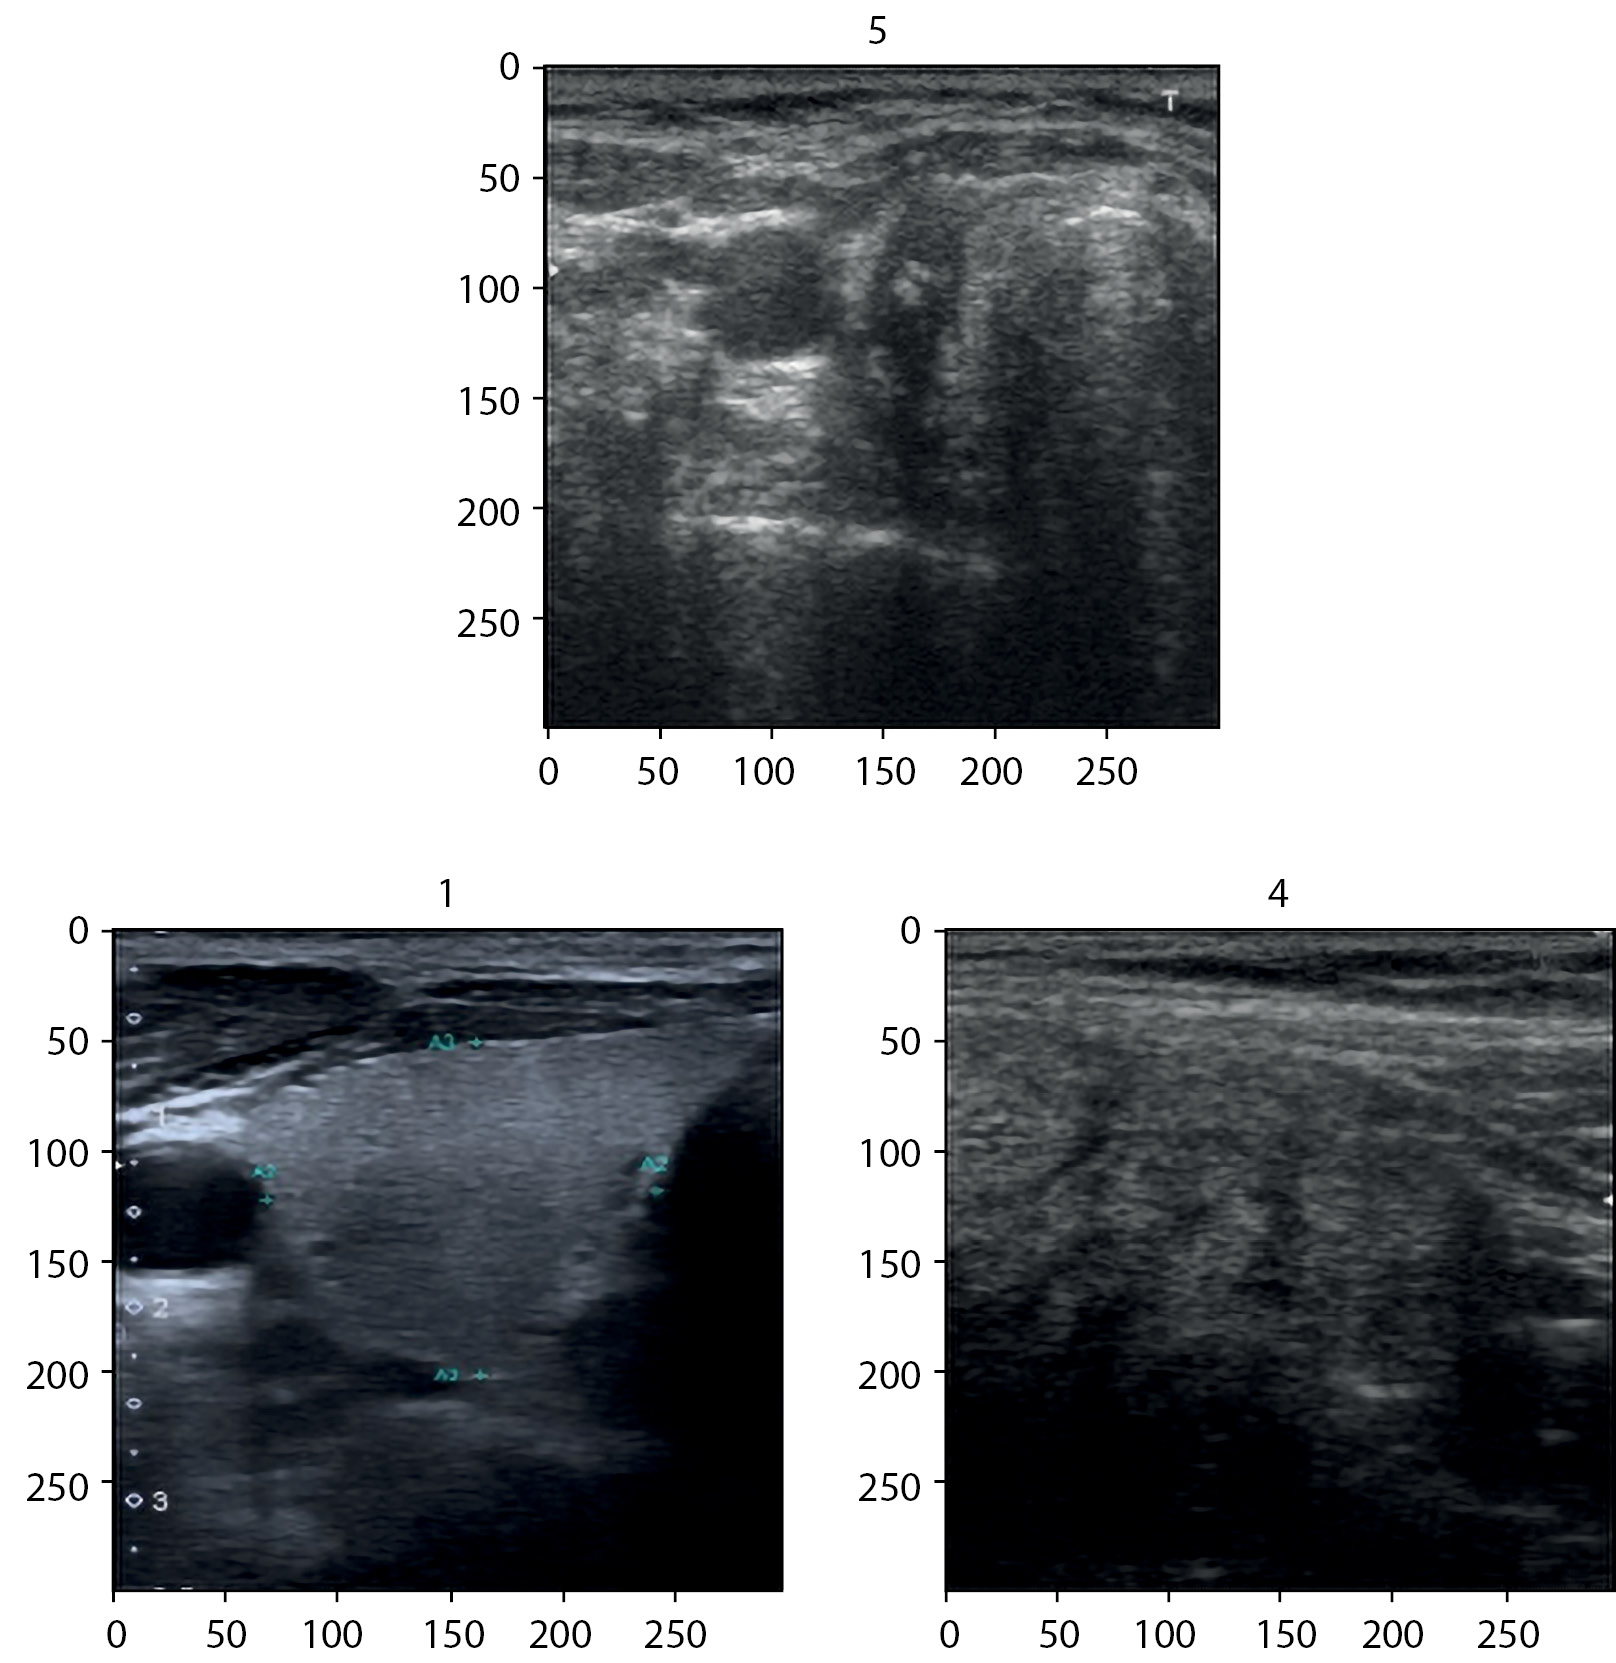

8. Рис. 8. Примеры распределения эхограмм щитовидной железы по категориям Eu-TIRADS. | |